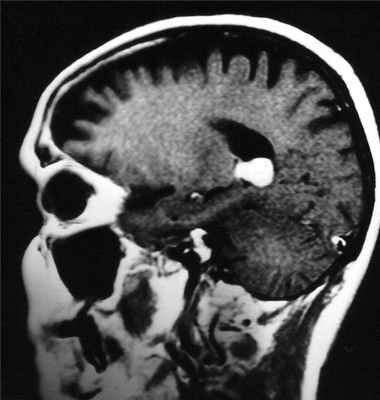

МРТ головного мозга. Субфронтальная менингиома. Сагиттальная Т2-взвешенная МРТ.

При МРТ головного мозга выявляется образование с широким основанием. Гиперостоз, часто видимый при КТ и на рентгенограммах, при МРТ головного мозга выглядит как утолщение внутренней костной пластинки свода черепа. Кальцинаты, обнаруживаемые при КТ в 20% наблюдений, при МРТ не видны. Опухоль при МРТ довольно однородная по структуре. Прорастание костей свода черепа видно отчетливо как участок повышенного сигнала на МРТ головного мозга любого типа в резко гипоинтенсивной кости. Сигнал от опухолевого узла на Т2-зависимых МРТ зависит от гистологического подтипа: относительно низкой интенсивности (между белым и серым веществом) при фибробластном и высокой при ангиобластном и синтициальном. Отек выражен в различной степени в каждом конкретном случае. Ряд МРТ признаков очень характерен для менингиомы: полоса ликвора между опухолью и тканью мозга, смещение окружающих сосудов. Они отражают неинвазивный характер роста. Смещенную и вовлеченную твердую мозговую оболочку иногда удается визуализировать при МРТ после введения гадолиния, особенно на корональных МРТ срезах. Усиление сигнала при МРТ с контрастированием от оболочки над опухолью с распространением в стороны (симптом “хвоста”) не абсолютно специфично и встречается при МРТ как при менингиоме, так и при лептоменингиальных метастазах. Однако при глиальных опухолях и невриноме при МРТ оно не описано. При обследовании пациентов методом МРТ в СПб с менингиомами серпа (фалькс-менингиомы) и намёта мозжечка рекомендуется делать МР-венографию для определения компрессии синуса и его проходимости. В наших центрах это обязательное исследование перед операцией. На открытом МРТ венография также легко выполнима. Не все центры МРТ СПб придерживаются этой методики.